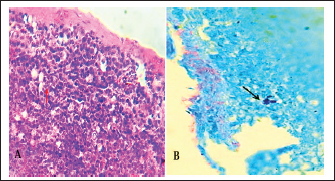

The normal histological view of the spleen sections showed a normal lymphoid follicles and normal splenic sinusoidal red pulp with normal population of megakaryocytes (Fig. 9), compared with the histopathological figures of the infected spleen that showed marked atrophy of lymphoid follicles with multiple focal cellular depletion and mild congestion of splenic sinusoid and focal hemorrhage with presence of fibrin thrombi (Fig. 10), other figures showed sub capsular degeneration of lymphoid tissue with infiltration of leukocytes. The magnification of these figures of spleen shows chlamydial inclusion bodies of C. psttaci within the cytoplasm of macrophages (Fig. 11).

Fig. 9. A). Section of spleen (control) shows: normal lymphoid follicles (black arrow) and normal splenic sinusoidal red pulp (red arrow). H&E stain.100x. B). Section of spleen (control) shows: normal lymphoid follicles and normal splenic sinusoid with normal population of megakaryocytes and splenic cords. H&E stain.400x.

Fig. 10. A). Section of chlamydial-infected spleen shows: atrophy of lymphoid follicles with multiple focal cellular depletion (red arrows) and congestion with distention of splenic sinusoid (black arrow) and focal hemorrhage (yellow arrow). H&E stain 100x. B). Section of spleen (infected) shows chlamydial inclusion bodies (IB) within the cytoplasm of macrophages (black arrows). H&E stain 400x.

Fig. 11. A). Section of spleen (infected) shows subcapsular degeneration of lymphoid tissue with infiltration of leukocytes and chlamydial inclusion bodies (Red arrow). H&E stain 400x. B). Individual chlamydial inclusion bodies (IB) of C. psittaci stained purple within the cytoplasm of macrophages (Black arrow). Giemsa stain 400x.